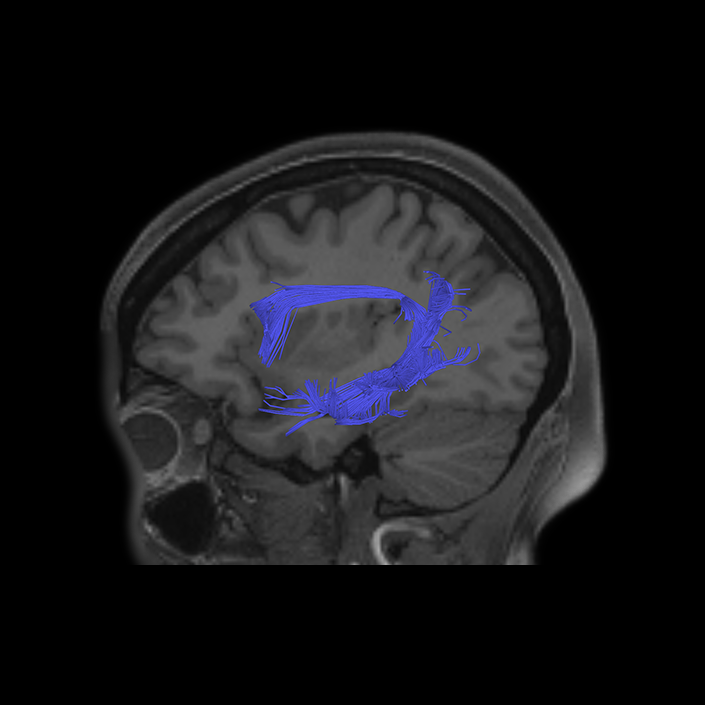

ᐅ SummaryArea 44: part of the inferior frontal gyrus of the lateral frontal lobe. Translates abstract and intentional information in the prefrontal cortex to more detailed representations to help guide the production of verbal and manual actions. In addition to its known association with Broca's area, is sometimes represented as part of Broca's complex ᐅ Where is it?Area 44 is at the posterior most part of the inferior frontal gyrus. It is the anterior bank of pars opercularis of the IFG. ᐅ What are its borders?Area 44 borders area 45 anteriorly and area 6r posteriorly. Area 8C is its medial border and its inferior border is wedged between then upper borders of Areas 6R and 6V. Its superior edge borders IFSp and IFJa. Its opercular surface is FOP4. ᐅ What are its functional connections?Area 44 demonstrates functional connectivity to areas SFL, IFSp, IFJa, 45, 47s, 47L, 9a, 9m, 8AV, 8BL and 8C in the dorsolateral frontal lobe, area 8BM in the medial frontal lobe, area 55b in the premotor areas, areas FOP5, AVI and PSL in the insula- opercular region, areas TGd, STSdp and STSvp in the temporal lobe, areas PFm, and PGi in the inferior parietal lobe, and no areas in the medial parietal lobe. ᐅ What are its white matter connections?Area 44 is structurally connected to the arcuate/SLF and the FAT. Connections with the arcuate/SLF project posteriorly and wrap around the Sylvian fissure to the middle temporal gyrus to end at TE1a and TE1m. There are also projections from the arcuate/SLF before it terminates to parcellations A5 and STSdp. The majority of the inferior connections of the frontal aslant tract end at 44, the tract is connected superiorly to superior frontal gyrus parcellations SFL, 6ma and s6-8. Local short association bundles are connected with 45 and 8C. White matter tracts from 44 in the right hemisphere have less consistent connections with the arcuate/SLF. ᐅ What is known about its function?Area 44 translates abstract and intentional information in the prefrontal cortex to more detailed representations to help guide the production of verbal and manual actions. Area 44, in addition to its known association with Broca's area, is sometimes represented as part of "Broca's complex", including Brodmann Areas 45, 46, 47 and the mesial supplementary motor area of 6, which contribute to a frontal-subcortical circuit. The right pars opercularis has also been implicated in cognitive inhibition in the overall context of working memory. |

DTI image |

ᐅ SummaryArea 45: part of the inferior frontal gyrus of the lateral frontal lobe. In addition to its known association with Broca's area, is sometimes represented as part of Broca's complex ᐅ Where is it?Area 45 is the lateral surface of pars triangularis of the IFG. ᐅ What are its borders?Area 45 borders area 47L anteriorly and area 44 posteriorly. Its superior edge borders area p47r, IFSa, and IFSp. Its opercular surface is conveniently named FOP5 ᐅ What are its functional connections?Area 45 demonstrates functional connectivity to areas SFL, IFSp, 44, a47r, 47s, 47L, 9a, 9p, 9m, 8AV, and 8BL in the dorsolateral frontal lobe, area 8BM in the medial frontal lobe, area 55b in the premotor areas, areas FOP5, and PSL in the insula-opercular region, areas TGd, TGv, TE1a, STSva, STSdp and STSvp in the temporal lobe, area PGi in the inferior parietal lobe, and area 31pd in the medial parietal lobe. ᐅ What are its white matter connections?Area 45 is structurally connected to the arcuate/SLF and IFOF. However, arcuate/SLF connections are not consistent across individuals. Connections with the arcuate/SLF project posteriorly and wrap around the Sylvian fissure to the middle temporal gyrus to end at TE1p. There are also projections from the arcuate/SLF before it terminates to parcellations A4 and PBelt. IFOF connections travel from 45 through the extreme/external capsule and continue posteriorly through the temporal lobe to end at occipital lobe parcellations V1, V2, V3 and V4. Local short association bundles connect with 44 and FOP4. ᐅ What is known about its function?Area 45, in addition to its known association with Broca's area, is sometimes represented as part of "Broca's complex", including Brodmann Areas 45, 46, 47 and the mesial supplementary motor area of 6, which contribute to a frontal-subcortical circuit. |

DTI image |